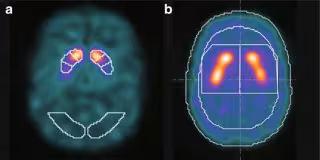

El Servicio de Medicina Nuclear del Hospital Universitario de Canarias (HUC) ha presentado un estudio que muestra que los pacientes con Parkinson tenían pérdidas anuales superiores al 11 por ciento de las neuronas dopaminérgicas frente al 5 por ciento de máximo de pérdida anual de los pacientes que no tenían realmente Parkinson.

Para el descubirmiento ha contado con la aplicación de un nuevo sistema de 'software' que puede permitir descartar el Parkinson en personas con síndrome parkinsoniano incierto, un diagnóstico que suele darse cuando los pacientes tienen síntomas no concluyentes o atípicos o existe duda del neurólogo sobre la patología, ya sea por alguna interacción con la medicación o por la interpretación de la imagen por parte de los especialistas de medicina nuclear.

El estudio del HUC, que ha utilizado un sistema de 'software' de imagen desarrollado por la división de Pharmaceutical Diagnostics de GE Healthcare, realiza un análisis cuantitativo y comparativo de los resultados de dos escáneres comparativos realizados a 30 pacientes con síndrome parkinsoniano de etiología Incierta escogidos entre más de 1.200 estudios.

El 'software' utilizado por los profesionales del hospital canario se utiliza en concreto en pacientes con 'estudios previos inconclusivos', cuantifica la pérdida de neuronas dopaminérgicas en términos porcentuales, y compara con poblaciones de referencia.